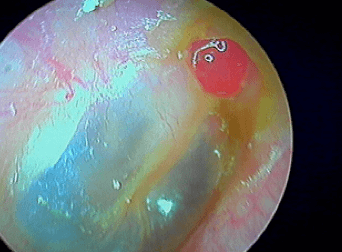

12/1 Glomus tympanique ou paragangliome tympanique

Tumeur rouge battante derrière un tympan normal, à ne pas confondre avec une otite séromuqueuse dont le liquide "bat" avec les battements des vaisseaux intratympaniques.

Ici une oreille droite, ce n'est pas une sténose de la paroi postérieure du CAE de l'oreille droite car elle "battait", j'ai suspecté une déhiscence méningée...